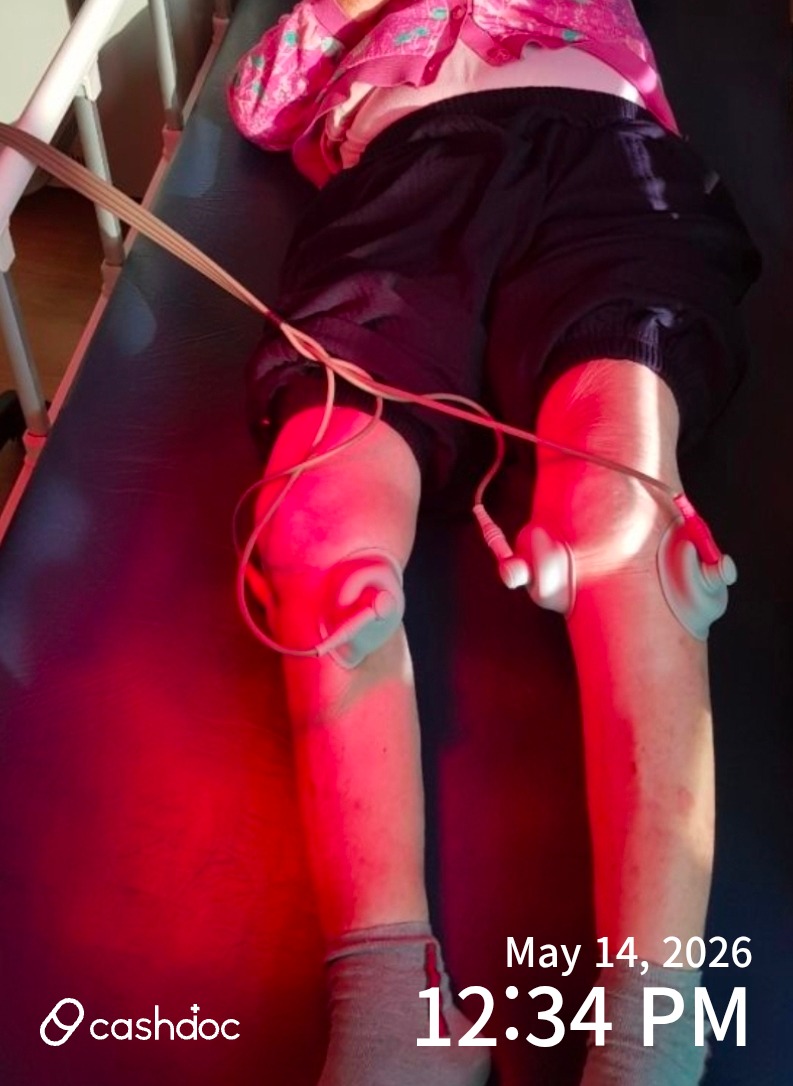

무릅뼈부어서. 튀어오른상태. 꾸준한물리치료덕분에. 정상으로 돌아왔습니다

무릅뼈부어서. 튀어오른상태. 꾸준한물리치료덕분에. 정상으로 돌아왔습니다